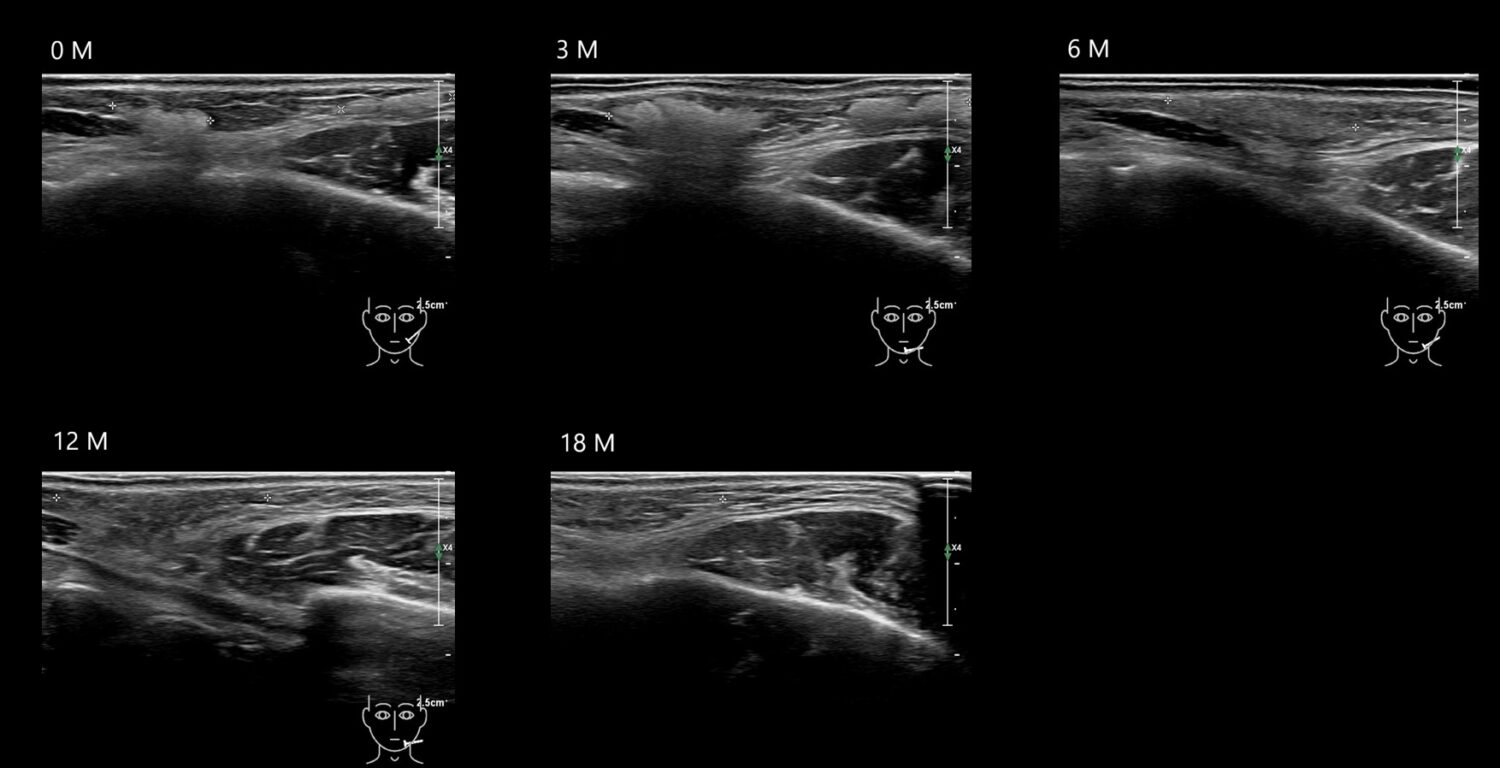

HAca12e